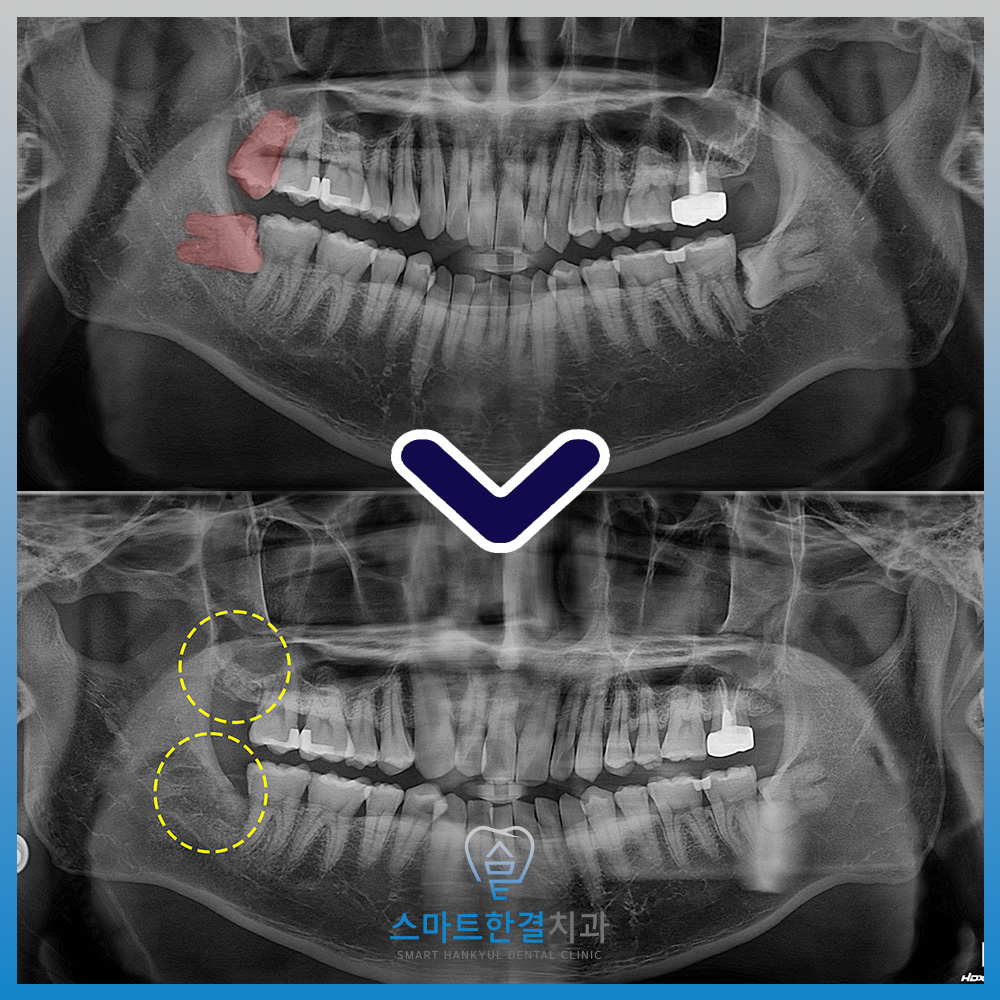

위, 아래 사랑니를

발치를 한 모습인데요.

주변 조직에 손상 없이

깔끔하게 발치를 했습니다.^^

아래 사랑니는 올바르게 나지 않고

누워 있기 때문에

한 번에 발치를 하지 못해요.

그래서 치아를 분할하고

머리와 뿌리를 나눠서

발치를 해야 하는데요.

치아를 감싸고 있는 뼈를

가능한 한 삭제 없이

발치를 진행하였어요.

그리고 위쪽 사랑니는

바르게 자라 있기 때문에

무리 없이 발치를 진행했어요~